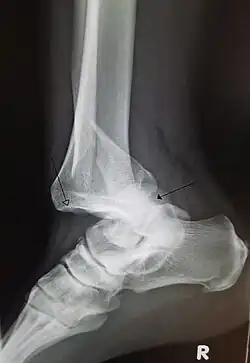

| A traumatic dislocation of the tibiotarsal joint of the ankle with distal fibular fracture. Open arrow marks the tibia and the closed arrow marks the talus. | |